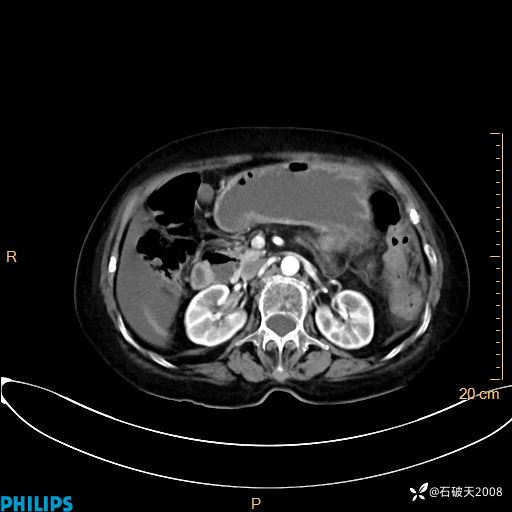

静脉期